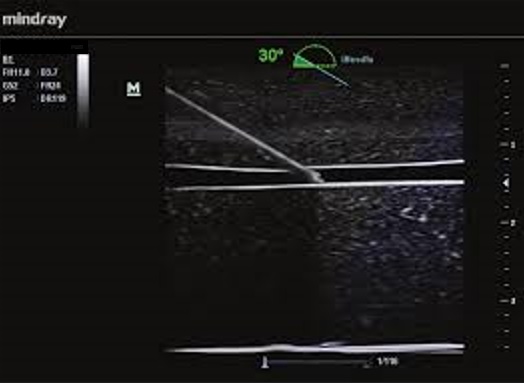

iNeedle - Vylepšenie vizualizácie pomocou ihly iNeedle

iNeedle (kontrastná vizualizácia punkčnej ihly)

iNeedle: Kontrastné zobrazenie bioptickej ihly.

iNeedle: Kontrastné zobrazenie bioptickej ihly.

iNeedle - Vylepšenie vizualizácie pomocou ihly iNeedle